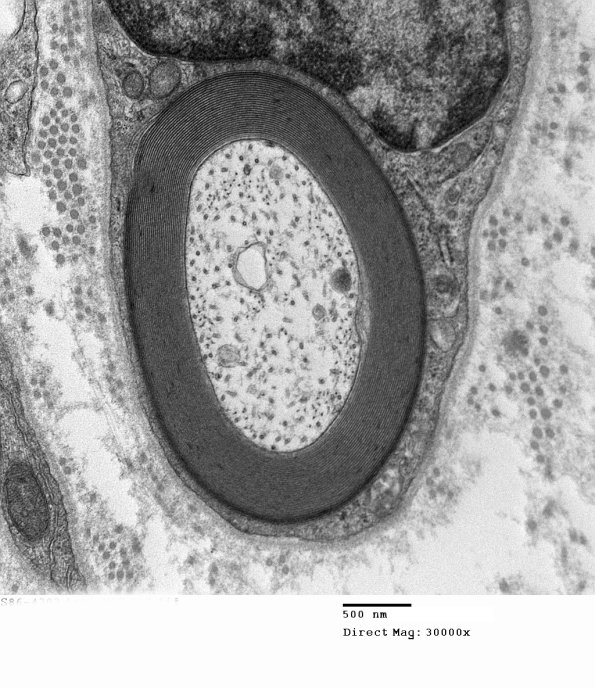

Washington University Experience | PERIPHERAL NEUROPATHY | 2 NORMAL AXON | 9A3 Normal axon (Case 9) 007 - Copy

Unmyelinated axons (and small myelinated axons) tend to have increased numbers of microtubules compared to neurofilaments which predominate in large myelinated axons. (electron micrograph)